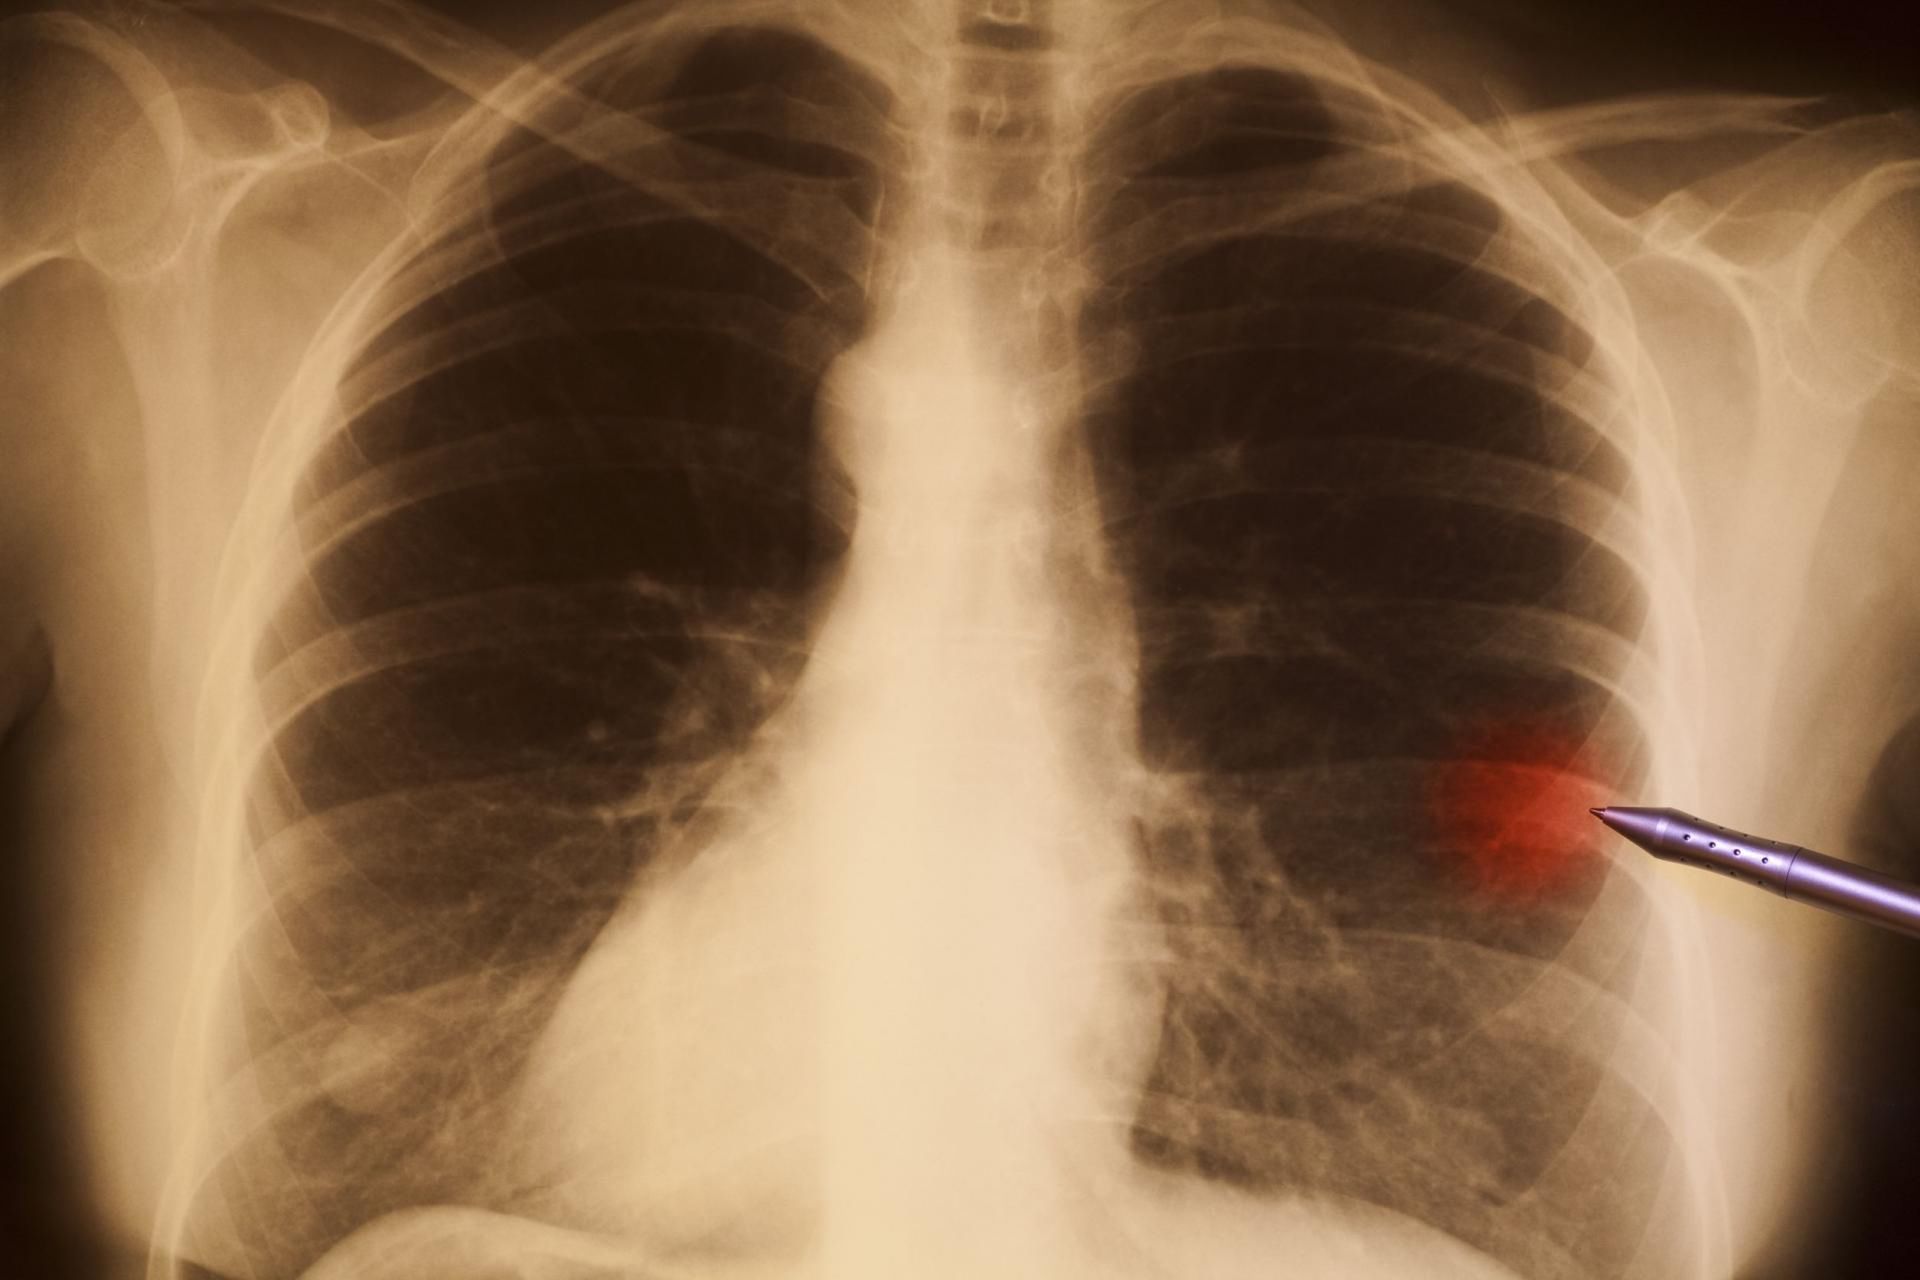

Rak płuc

Lek Alecensa zahamował rozwój raka płuc o 15 miesięcy, w porównaniu do leku Xalkori, który był podawany 303 osobom chorującym na tą chorobę. Alecensa również spowodował zmniejszenie pogarszania się stanu zdrowia pacjenta o kolejne 26 miesięcy, w porównaniu do 11 miesięcy, dla osób zażywających Xalkori. Tylko 9 proc. pacjentów którym podawano Alecensę, miało przerzuty choroby do mózgu. Dla porównania, aż 41 proc. pacjentów przyjmujących Xalkori, doświadczyło przejścia choroby z płuc do mózgu.